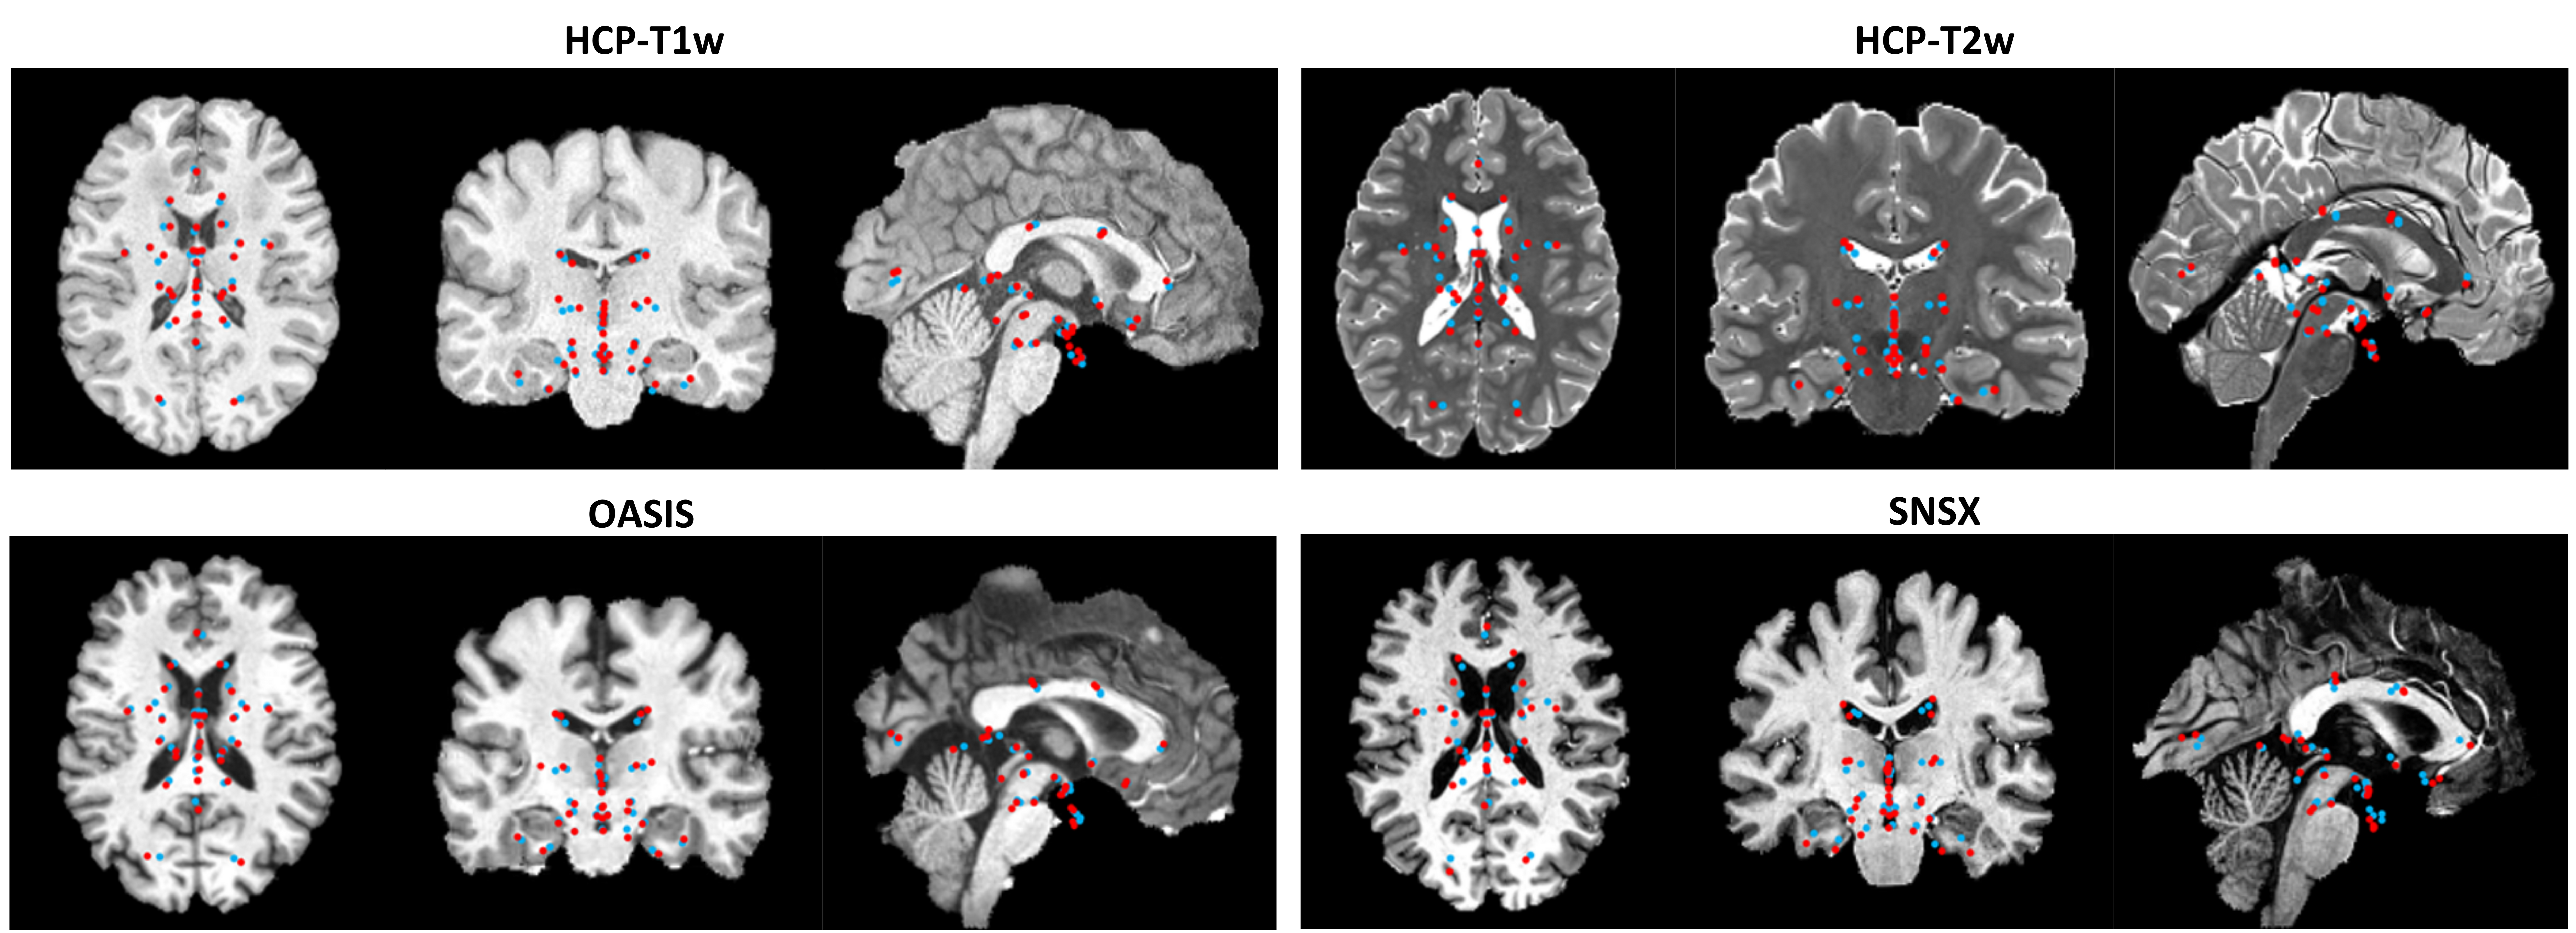

Refer to caption

Figure 2: Qualitative comparison of anatomical landmark detection results using the proposed technique, illustrated on coronal, axial, and sagittal mid-slices (red=ground truths, blue=automatic results) for samples across all datasets. Note that the landmarks shown are projections of 3D points in each canonical view.